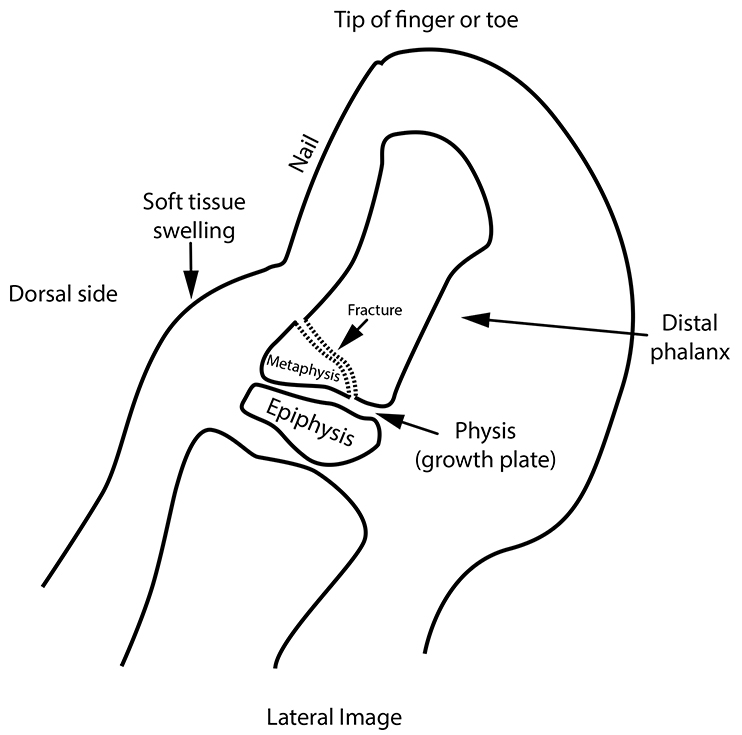

As a result, on the x-ray (as well as on physical exam) the digit shows soft tissue swelling just proximal [in the direction of the ankle or wrist] to the nail of the digit.

Because such fracture often entails a small break in the skin at the side of the nail, bacteria may gain access to the inside of the finger or toe. The nail bed is highly vascular, as is the nearby metaphysis. This means that infection could easily travel within the toe or finger to the fractured metaphysis (see diagram 2). This means an infection of the bone (known as osteomyelitis) can occur in that metaphysis.

Be aware that it is only the lateral image (side view) that shows all the structures mentioned above that can be injured by stubbing, as on Diagram 2. It is also important not to have any finger or toe overlying the x-rayed digit.

The Salter 2 fracture fragment of the metaphysis is often quite subtle, so the zooming (enlarging) of the original lateral image is important in its detection on the original lateral x-ray.